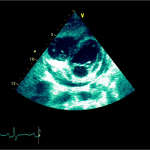

Ecocardiografia transtoracică

- Formaţiune hiperecogenă cu suprafaţa neregulată, care tapetează peretele liber al VD, grosime de 12 mm

- Dispusă de sub planul valvei tricuspide până in apropierea conului de ejecţie al valvei pulmonare

- SIV aplatizat

Ecografia transesofagiană:

Confirmă datele de la ecografia transtoracică